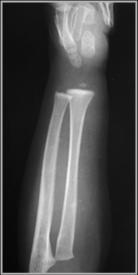

Lead poisoning